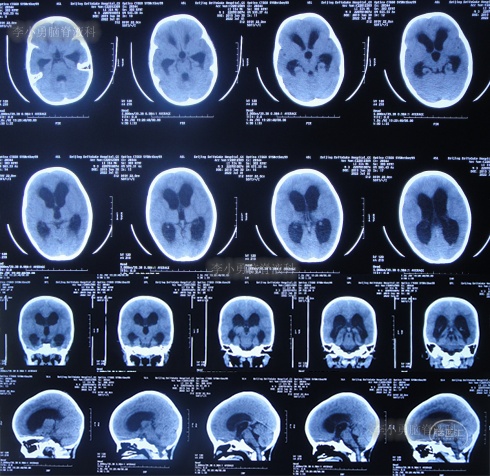

入院当天查头颅CT示脑室扩张(图-8)。

图-8:2022年7月1日入院时头颅CT

住院治疗18天即2022年7月18日,查头颅CT示脑室有缩小(图-12)。

图-12:2022年7月18日头颅CT

住院治疗63天即2022年9月1日,常规查头颅CT示脑室引流术后状态(图-15)。

图-15:2022年9月1日头颅CT

2022年10月12日(住院治疗104天),已夹闭脑室引流管3天,查头颅CT示脑室未见异常(图-17)。

图-17:2022年10月12日头颅CT

2022年10月19日(住院治疗111天),拔除了脑室引流术,拔管前和拔管后头颅CT(图-18)对比。

图-18:2022年10月19日拔管前后头颅CT对比

2022年10月25日(李小勇脑脊液科治疗117天),出院时:精神状态挺好,大小便正常,虽右腿走路稍差但走路速度变快,变稳(图-19);出院时头颅CT示未见异常(图-20)。

图-20:出院时头颅CT